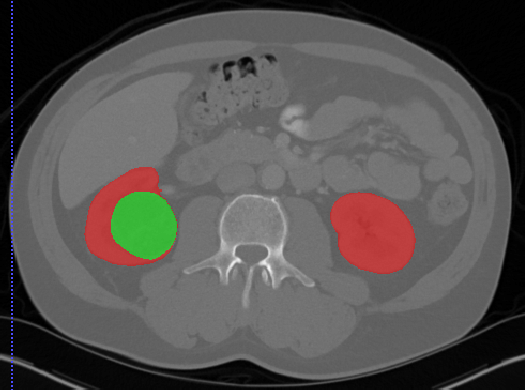

肾脏

Kits19

| Kits19 | 肾脏/肾肿瘤 | 分割 |